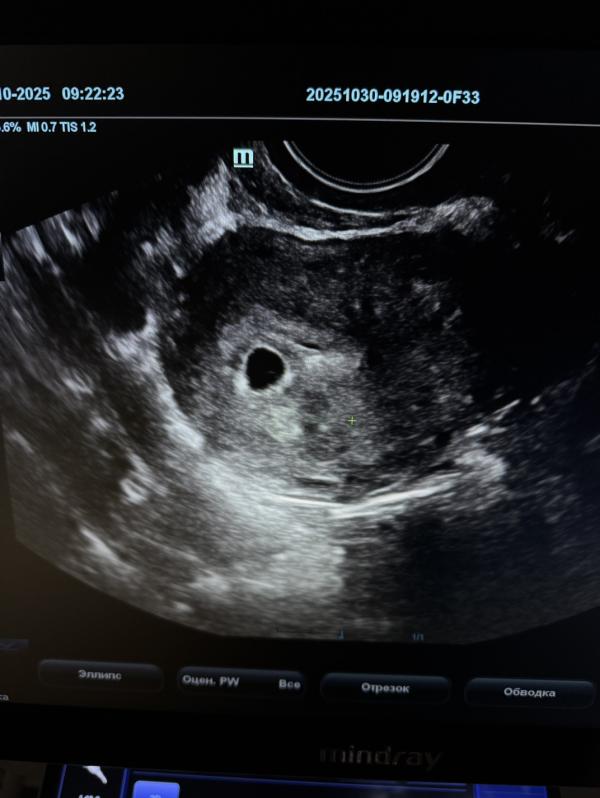

Что можно увидеть на УЗИ на 5 неделе беременности🤰

Матка: увеличена

В полости матки определяется ПЛОДНОЕ ЯЙЦО

Размер: 5–10 мм (соответствует 5 акушерской неделе).

Внутри плодного яйца визуализируется желточный мешок.

Диаметр: примерно 2–4 мм.

Эмбрион: на 5 неделе ещё не визуализируется, что является вариантом нормы.